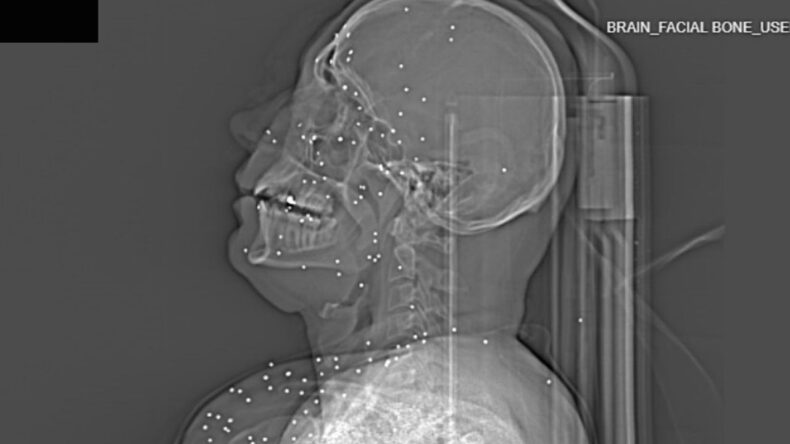

İngiliz gazetesi The Guardian ve söz konusu bilgilerin doğruluğunu teyit eden Factnameh'nin gerçekleştirdiği ortak araştırmada, ülkenin büyük şehirlerinden birinde yer alan bir hastaneden elde edilen 75'ten fazla röntgen ve bilgisayarlı tomografi görüntüsü yayınlandı.

Bu görüntüler, güvenlik güçlerinin yüksek kalibreli silahlar ve birdshot mühimmatı kullandığına dair iddiaları destekliyor. Röntgenlerin büyük bölümünde, protestoculara karşı “birdshot” olarak adlandırılan mermilerin kullanıldığı belirtiliyor.

Uzmanlar, bu tür mühimmatların uzak mesafelerde geniş bir alana yayıldığını, ancak yakın mesafeden atıldığında ciddi ve hayati tehlike içeren yaralanmalara yol açabileceğini ifade etti.

Saldırıların çoğunlukla yüz, göğüs ve genital bölgelerde yoğunlaştığı da dikkatlerden kaçmadı. 2022 yılında başlayan “Kadın, Yaşam, Özgürlük” protestolarında da benzer yaralanma örüntüleri gözlenmişti.

Guardian'a konuşan İranlı doktorlar, protestocuların özellikle göz, göğüs ve genital bölgelerinin hedef alındığını ifade etti. Bazı sağlık çalışanları, pek çok hastada görme kaybı meydana geldiğini ve bunu yaşayanlar arasında çocukların da bulunduğunu belirtti.